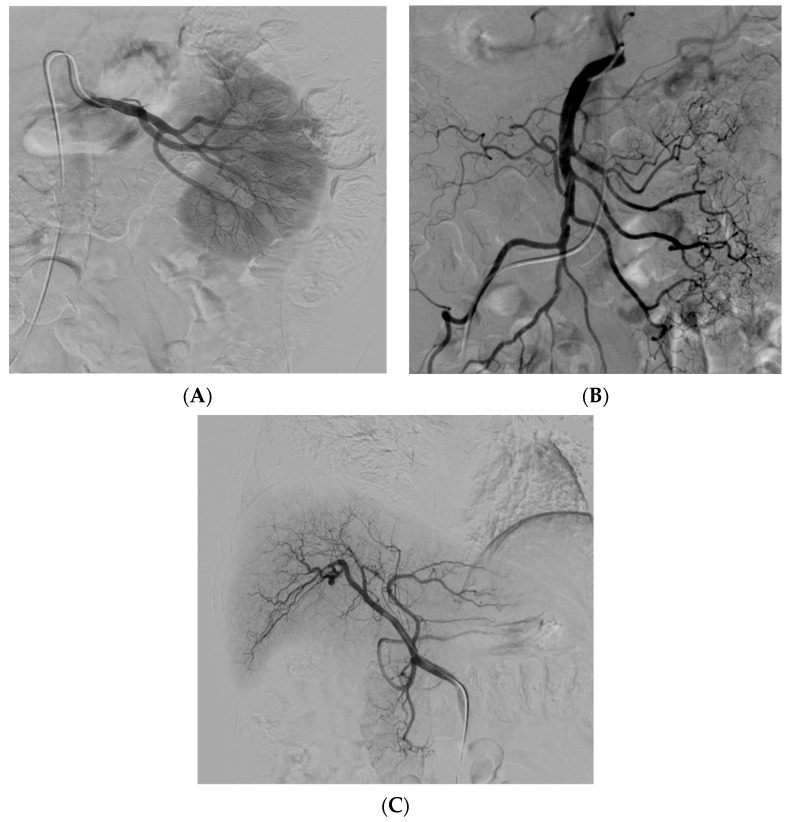

經(jīng)動脈干細胞注射(TASI)可能被認為是一種理想的選擇性遞送方法,在所需器官中具有最佳分布和高干細胞濃度。在組織取樣和干細胞分離處理(自體或異體)之后,該過程基本上包括通過動脈通路(最常見的是股動脈)引入導(dǎo)管。然后,在熒光鏡和造影劑引導(dǎo)下,將導(dǎo)管放置在所需的供血動脈(肝動脈、腸系膜動脈或腎動脈)中,以進行隨后的干細胞注射。圖2)。

圖2:腎 (?A?)、腸系膜上動脈 (?B?) 和肝動脈 (?C?) 的血管造影插管

圖2

導(dǎo)管定位確保對所需組織進行選擇性治療,避免非目標干細胞輸注。